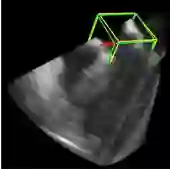

利用2891次心脏超声检查的数据集,Ghesu等结合深度学习和边缘空间学习进行医学图像检测和分割[12]。“大参数空间的有效探索”和在深度网络中实施稀疏性的方法相结合,提高了计算效率,并且与同一组发布的参考方法相比,平均分割误差减少了13.5%,八位患者的检测结果如图4所示。Brosch等人利用MRI图像上研究多发性硬化脑病变分割的问题。开发了一种3D深度卷积编码器网络,它结合了卷积和反卷积[13],图5.增加网络深度对病变的分割性能的影响。卷积网络学习了更高级别的特征,并且反卷积网络预进行像素级别分割。将网络应用于两个公开的数据集和一个临床试验数据集,与5种公开方法进行了比较,展现了最好的方法。Pereira等人的研究中对MRI上的脑肿瘤分割进行了研究,使用更深层的架构,数据归一化和数据增强技巧[14]。将不同的CNN架构用于肿瘤,该方法分别对疑似肿瘤的图像增强和核心区域进行分割。在2013年的公共挑战数据集上获得了最高成绩。

图4示例图像显示了不同患者的检测结果从测试集。检测到的边界框以绿色显示,标准的框以黄色显示。原点位于每个框中心的线段定义相应的坐标系